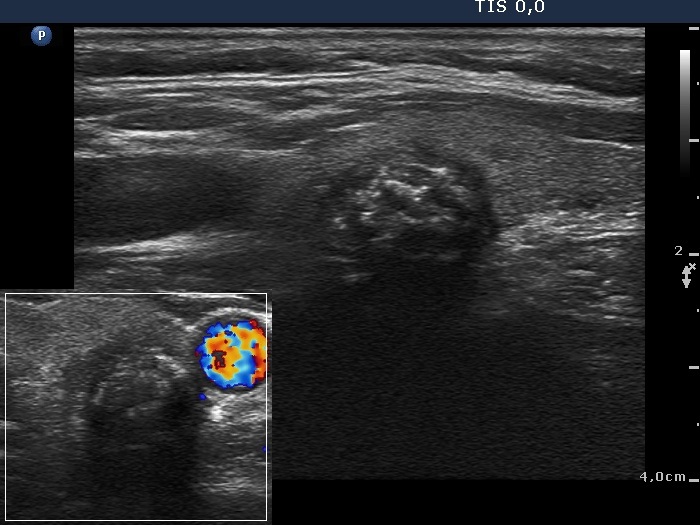

Granulation around surgical thread (histological diagnosis) - case 411 |

Papillary carcinoma (histological diagnosis) - case 779 |

Here is another example of the differential diagnostic problem caused by granulation around surgical thread. Again, there is no difference between the ultrasound presentations of these cases except for the vascularization. The right, malignant case cannot be a granulation around surgical thread which is always avascular; however, this is not a great revelation in a patient who has not been operated. Conversely, the lack of vascularization by no means excludes the possibility of a carcinoma.